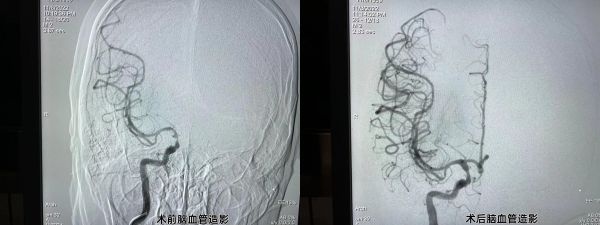

脑血管造影术前、术后对比。

就这样,一场与时间赛跑的“接力赛”正式打响,两支不同的专业团队医生,同时上台介入手术。当日20时许,该院胸痛中心负责人、心血管内科主任邓昭武带领胸痛团队为李先生进行了冠状动脉造影,发现右侧冠状动脉中远段闭塞,立即行冠状动脉球囊扩张术+支架植入术;22时,朱灿敏带领卒中中心团队进行“接台”,并随即为李先生行全脑血管介入手术,脑血管造影见:右侧颈内动脉末端次全闭塞,血栓形成;右侧大脑前动脉闭塞。立即行颅内动脉取栓术;23时30分,李先生手术成功结束,安全转回神经内科病房。